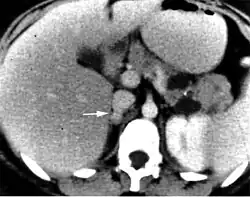

CT imaging of a pheochromocytoma as part of VHL disease

Pheochromocytoma is a neoplasm composed of cells similar to the chromaffin cells of the mature adrenal medulla. Pheochromocytomas occur in patients of all ages, and may be sporadic, or associated with a hereditary cancer syndrome, such as multiple endocrine neoplasia (MEN) types IIA and IIB, neurofibromatosis type I, or von Hippel–Lindau syndrome. Only 10% of adrenal pheochromocytomas are malignant, while the rest are benign tumors. The most clinically important feature of pheochromocytomas is their tendency to produce large amounts of the catecholamine hormones epinephrine (adrenaline) and norepinephrine. This may lead to potentially life-threatening high blood pressure, or cardiac arrhythmias, and numerous symptoms such as headache, palpitations, anxiety attacks, sweating, weight loss, and tremor. Diagnosis is most easily confirmed through urinary measurement of catecholamine metabolites such as VMA and metanephrines. Most pheochromocytomas are initially treated with anti-adrenergic drugs to protect against catecholamine overload, with surgery employed to remove the tumor once the patient is medically stable.[17]